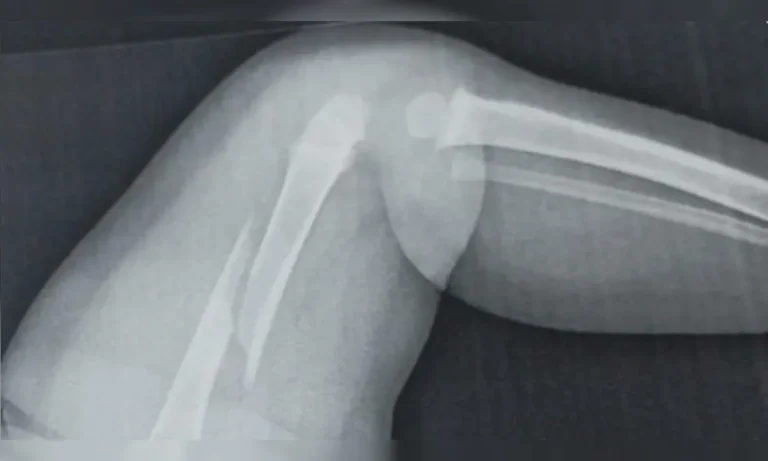

Polícia apura agressão contra bebê de um ano no PR após médicos acharem fratura antiga e lesão no fêmur 12 de fevereiro de 2026